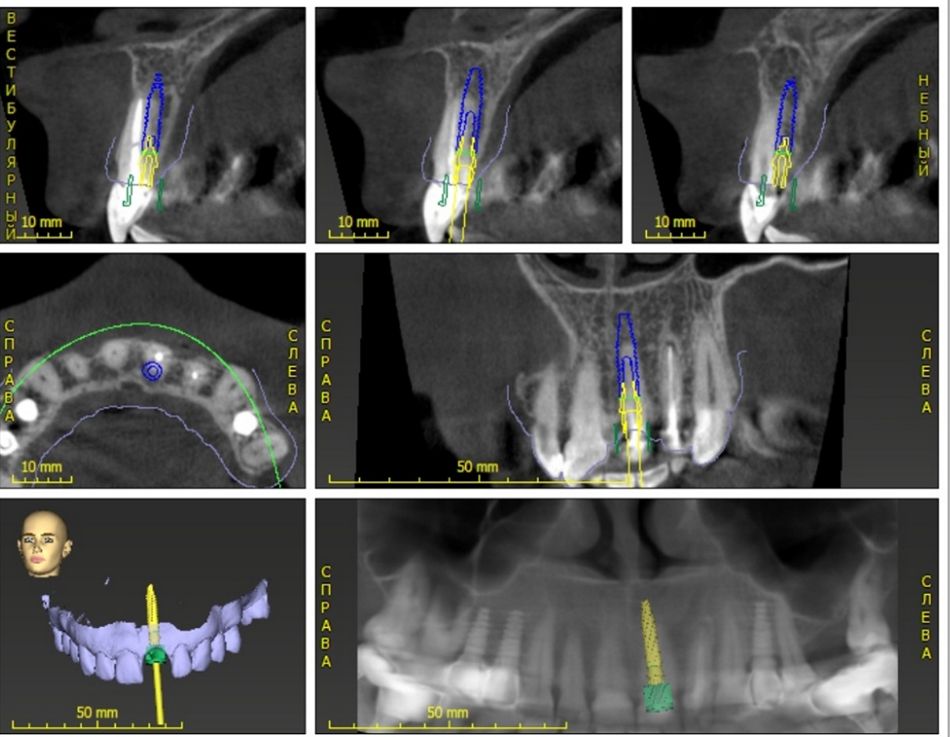

Based on the clinical and radiographic evaluation, the treatment strategy comprised atraumatic tooth extraction followed by immediate implant placement and restoration. Implant planning was based on models combined from CBCT and intraoral scans using coDiagnostiX® surgical planning software and 3shape smile composer. As evidenced in Figure 3, the implant restoration was planned based on a Straumann® BLT Roxolid®, SLActive® Ø3.3 x12 mm combined with an immediate temporary restoration with a prefabricated final Variobase® zirconia abutment. The latter was planned and designed, taking into account the anticipated post-extraction local soft tissue contours, using 3Shape Smile Composer® (Figure 4). Figure 5 illustrates the capabilities of the new coDiagnostiX® Virtual Tooth Extraction module to visualize and finely adjust the planned implant-prosthetic restoration in the context of the patient's local soft and hard tissue anatomy. The implant position was planned buccally with regard to the existing tooth's position to attain adequate primary stability, maximizing the buccal and coronal engagement of the implant, with an adequate emergence profile to support the future restorative crown.